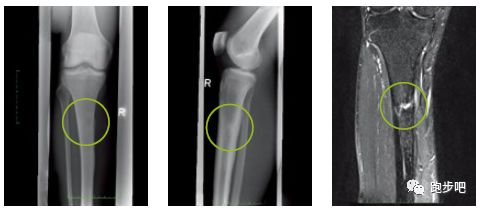

应力性骨折

症状:

●早期的应力性骨折通常表现为骨挫伤,也可能会伴随其他损伤(如前交叉韧带撕裂)。

●下肢没有受到过外部激烈的碰撞而出现突然性疼痛,而且这种疼痛使人不能继续跑步,或者很难继续跑步。

●单足站立时局部出现疼痛,或者单足跳时出现疼痛。

●用手指压痛处时出现钻心的疼痛感。

●疼痛点在完全停止跑步后在一段时间内会自然消除。